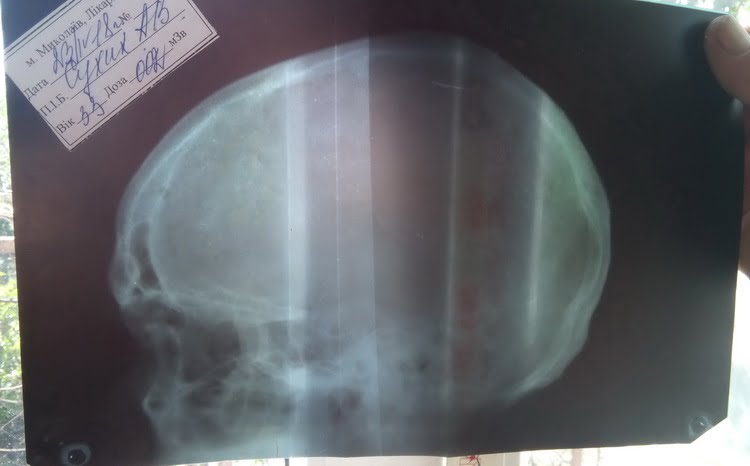

На следующий день, 23 апреля, мне было очень плохо, болела голова, болел нос. Я пошёл в нашу больницу (ЖЦРБ), мне там диагностировали перелом спинки носа, сотрясение головного мозга, повреждение мягких тканей лица (множественные ушибы, ссадины, гематомы), ушиб правого коленного сустава, ушиб пояснично-крестцового отдела позвоночника, нарушен вестибулярный аппарат, треснуты обе перепонки, и что я теряю слух, и что мне надо теперь делать капельницу каждые полгода, прописали курс лечения», — рассказал Анатолий, подтвердив свои слова медицинскими документами: